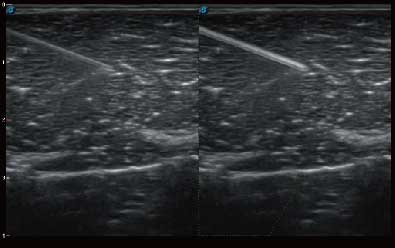

自动识别穿刺针进行声束智能偏转 手动修正多档调节 提高一次穿刺成功率

自动识别组织边界信息进行图像无损拼接 抖动抑制技术提高成像效果 完整显示较大病灶及组织,为临床提供可靠诊疗方案

0.5mm厚度的薄层切片显像,可清晰显示微小病灶的连续断面。